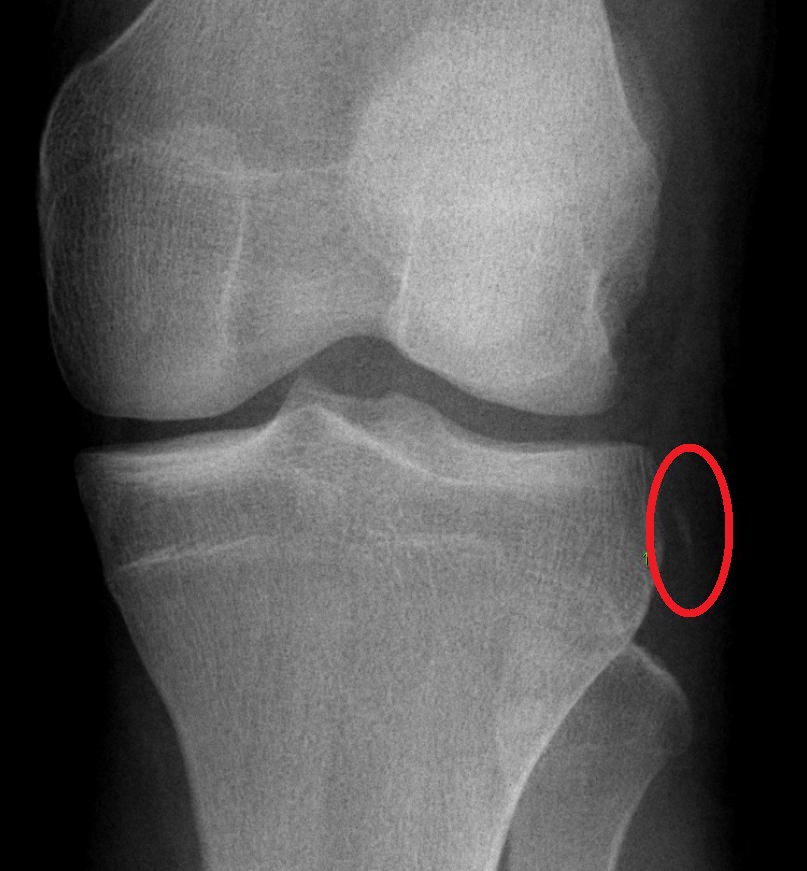

Knee with complete ACL rupture showing torn ligament, bone bruises on lateral femoral condyle and posterolateral...

Knee with medial meniscus tear (bucket-handle type) showing displaced meniscal fragment, joint effusion, and...

Degenerative knee with joint space narrowing, osteophytes, subchondral sclerosis, cartilage thinning, and Baker's cyst